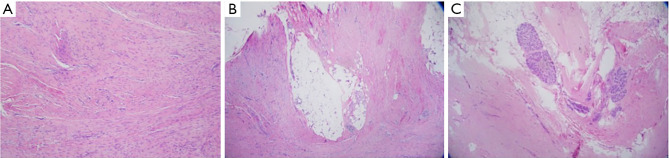

Case description: This is a case report of a 34-year-old female with a history of bilateral silicone implant placement who presented with bilateral breast masses. She reported a 6-month history of a 1-cm firm, palpable mass in the right breast without associated pain or growth. She had a family history of breast, pancreatic, and prostate cancer but no significant past medical history. Ultrasound-guided biopsy of the right breast and magnetic resonance imaging (MRI)-guided biopsy of the left breast both revealed fibromatoses. She underwent bilateral excisional biopsies and surgical pathology confirmed breast fibromatosis in the background of benign breast tissue with fibrocystic changes. The patient had an uncomplicated post-operative course.